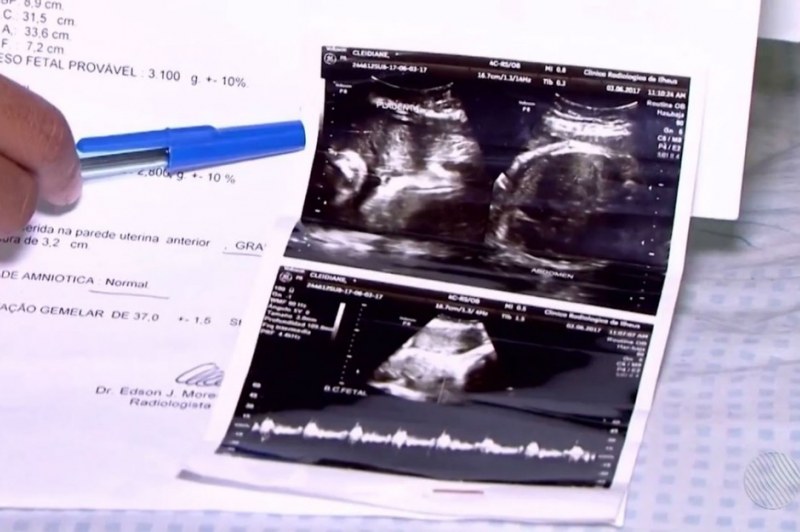

A dona de casa diz, no entanto, que a última ultrassonografia da gravidez dela foi feita no dia 3 de junho, quando ela estava com 37 semanas, e confirma que ela estava grávida de gêmeos e até descreve os dois fetos. A mulher também afirma que, antes do parto, ainda chegou a ser informada no hospital que os dois bebês estavam bem.

A delegada que investiga o caso, Andrea Oliveira, afirmou que a polícia ainda tenta esclarecer o que aconteceu. "Temos duas alternativas: ou a a ultrassonografia está errada, o laudo foi feito de forma errada, ou então realmente havia duas crianças e uma delas está desaparecida. Aí a gente tem que solucionar o caso e ver onde está essa criança", disse a delegada Andrea Oliveira.